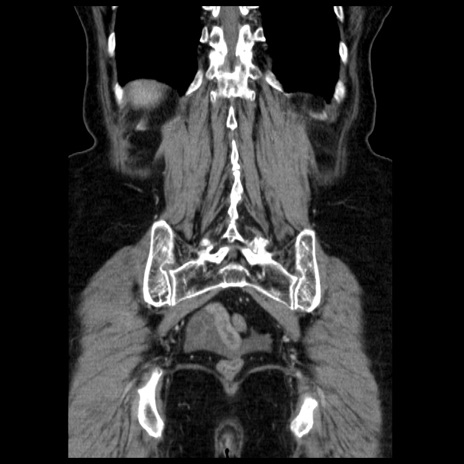

症例13(冠状断像)

【症例】70歳代女性

【主訴】腹痛、嘔吐

【現病歴】15時間程前(昨晩)より腹痛あり。今朝になっても症状の改善なく、嘔吐あり。腹痛も増悪あり、救急外来受診。

【既往歴】子宮癌全摘術後

【身体所見】意識清明、BP 121/72mmHg、P 74bpm、SpO2 100%(RA)、腹部:平坦・軟、腸雑音ほぼ聴取せず。下腹部・心窩部・臍左上に圧痛あり。反跳痛なし。

【データ】WBC 10600、CRP 0.15